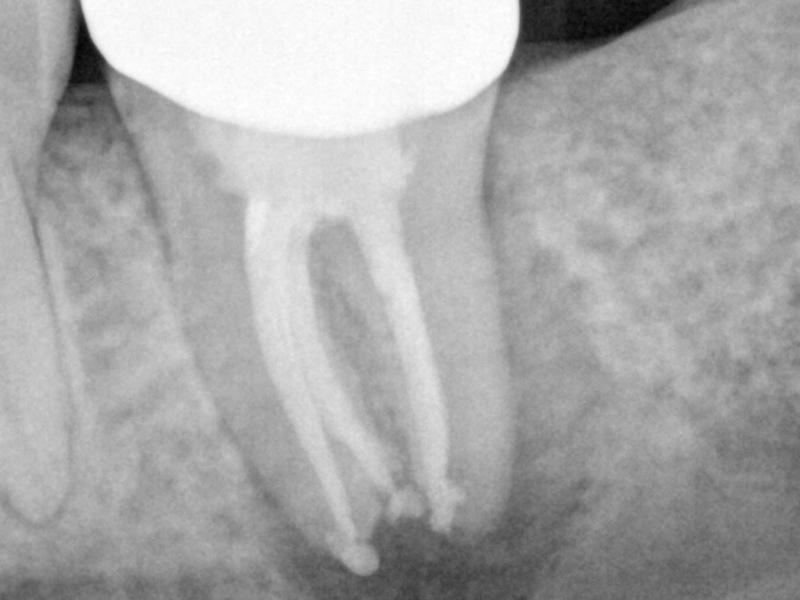

Recall